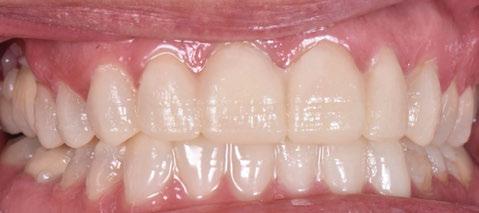

Terminada esta fase se elaboró una propuesta de diseño (CEREC,

SW 5.2, Dentsply Sirona) (Figuras 22-27), la cual fue materializada en dos tipos de materiales a partir de bloques cerámicos IPS Empress CAD y cerámica vítrea de disilicato de litio IPS E.max CAD (Figuras 28-30)

Finalmente, las restauraciones se cementaron adhesivamente (Figuras 31-35). En las piezas 16 y 17 se realizaron restauraciones cementoatornilladas como última fase de tratamiento. Se recomendó al paciente una férula de protección superior la cual fue elaborada mediante un flujo de trabajo digital (Figura 36)

Figura 33. Vista oclusal superior. Figura 34. Vista oclusal maxilar Inferior. Figura 31. Restauraciones cementadas, vista anterior superior. Figura 32. Restauraciones cementadas, vista anterior inferior. Figura 35. Vista en oclusión del caso terminado.